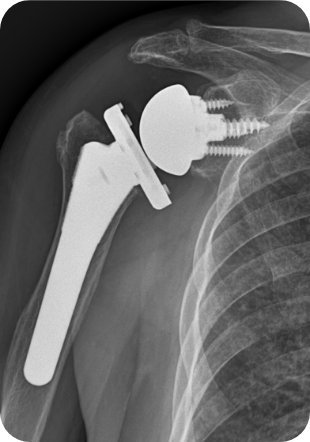

• ▲ 어깨인공관절 인공치환술 전

• ▲ 어깨인공관절 인공치환술 후

• 수술방법

상완골두만을 갈아끼우는 반치환성형술을 할 수도 있고, 견갑관절과 인공삽입물이 함께 삽입되는 전치환성형술을 하기도 합니다. 최근에는 역 전치환술이 개발되어 기존 인공관절의 단점을 보완하게 되었습니다.